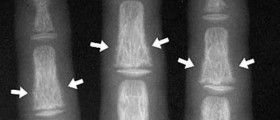

Calcium is the most important component when it comes to proper formation, development and strength of the bones and teeth. Together with phosphate it forms hydroxyapatite which is actually the compound the teeth and bones are made of. Since the bones are constantly reforming, they always need more and more calcium.

A healthy adult person requires somewhere between 1200 and 1300 milligrams of calcium per day. The requirements may vary depending on the built of the individual and other significant factors such as gender and age. Post menopausal and pregnant women also require much more calcium than usual. Since it cannot be obtained that easily from the ordinary diet, these persons are advised to take calcium supplements. If one needs to take calcium supplements, it is a very good idea to choose products which are known for the best purity, tolerance, absorbability and zero interactions with different body functions. There are three different types of calcium supplements and those include calcium citrate, calcium phosphate and calcium carbonate. Calcium carbonate is known for being very efficient in reducing the frequency of bowel movements which may eventually lead to development of constipation. This type of calcium supplements may also be held responsible for abdominal bloating and formation of gas. One should space out the dosages of the supplements throughout the day.